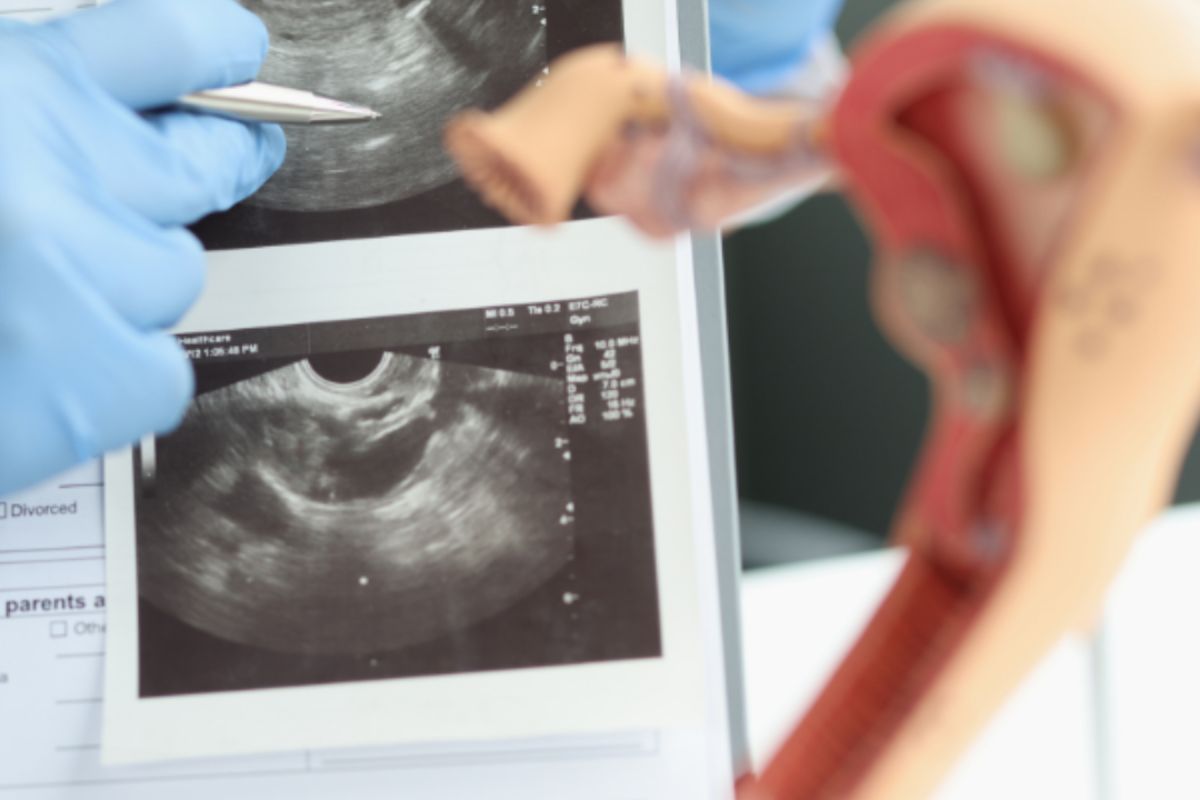

La sonohisterosalpingografía (SIS) es un procedimiento diagnóstico avanzado que utiliza ultrasonido y una solución salina estéril para evaluar la cavidad uterina y la permeabilidad de las trompas de Falopio. Este estudio mínimamente invasivo proporciona información valiosa sobre la salud reproductiva de la mujer.

La sonohisterosalpingografía ofrece una alternativa menos invasiva y sin radiación a la histerosalpingografía tradicional, permitiendo visualizar con claridad la anatomía uterina y tubárica en tiempo real.

Durante el procedimiento, se introduce cuidadosamente una pequeña cantidad de solución salina estéril a través del cérvix hacia el útero. Esto permite que el especialista visualice con claridad cualquier anormalidad como pólipos, miomas, adherencias o malformaciones uterinas, así como verificar la permeabilidad de las trompas de Falopio.